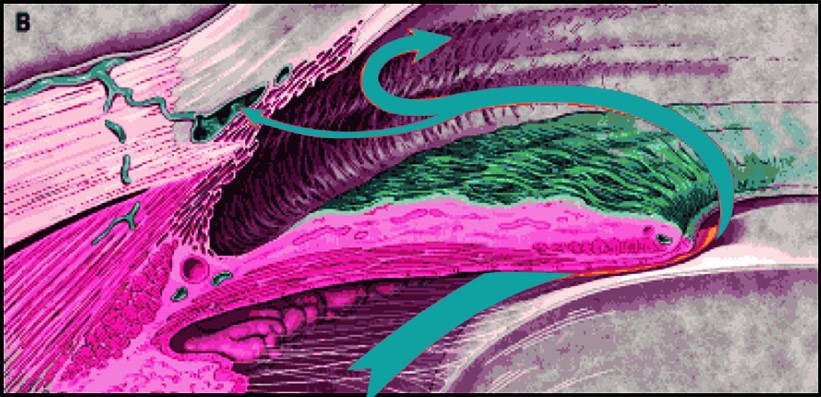

ABBILDUNG 1B: Beim Offenwinkelglaukom kann die produzierte Flüssigkeit nicht so schnell abfließen und verbleibt länger im Auge, wodurch sich der Augendruck erhöht, was zu Schäden und einem dauerhaften Sehverlust führen kann.

Übernommen von: Distelhorst JS, Hughes GM. Open-angle glaucoma. Am Fam Physician. 2003 May 1;67(9):1937-44.